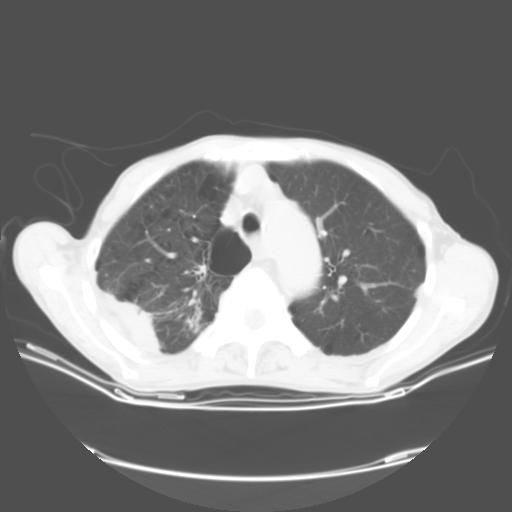

女,72岁,咳嗽一周余,突发右下肢无力二天。

来院做头颅+胸部ct平扫

胸部病变平扫35hu,增强强化至70hu

这个病人首先是胸部病变的定位到底是肺内还是肺外。仔细观察块影位于胸膜下,与胸膜间有透亮带,且近端血管未见明显推移而是引流样改变,形态分叶,说明这个病灶位于肺内胸膜下。很可能是腺癌,腺癌最易致颅内高密度转移灶。局部胸膜有侵犯。

本例颅内见多发大小不等高密度灶,有强化及水肿;另外,胸锁关节层面可能是第四胸椎及右侧肋骨起始部骨质欠连续,椎旁软组织肿胀,建议调骨窗观察。

诊断:右下肺癌伴颅内、胸椎、肋骨转移可能性最大。